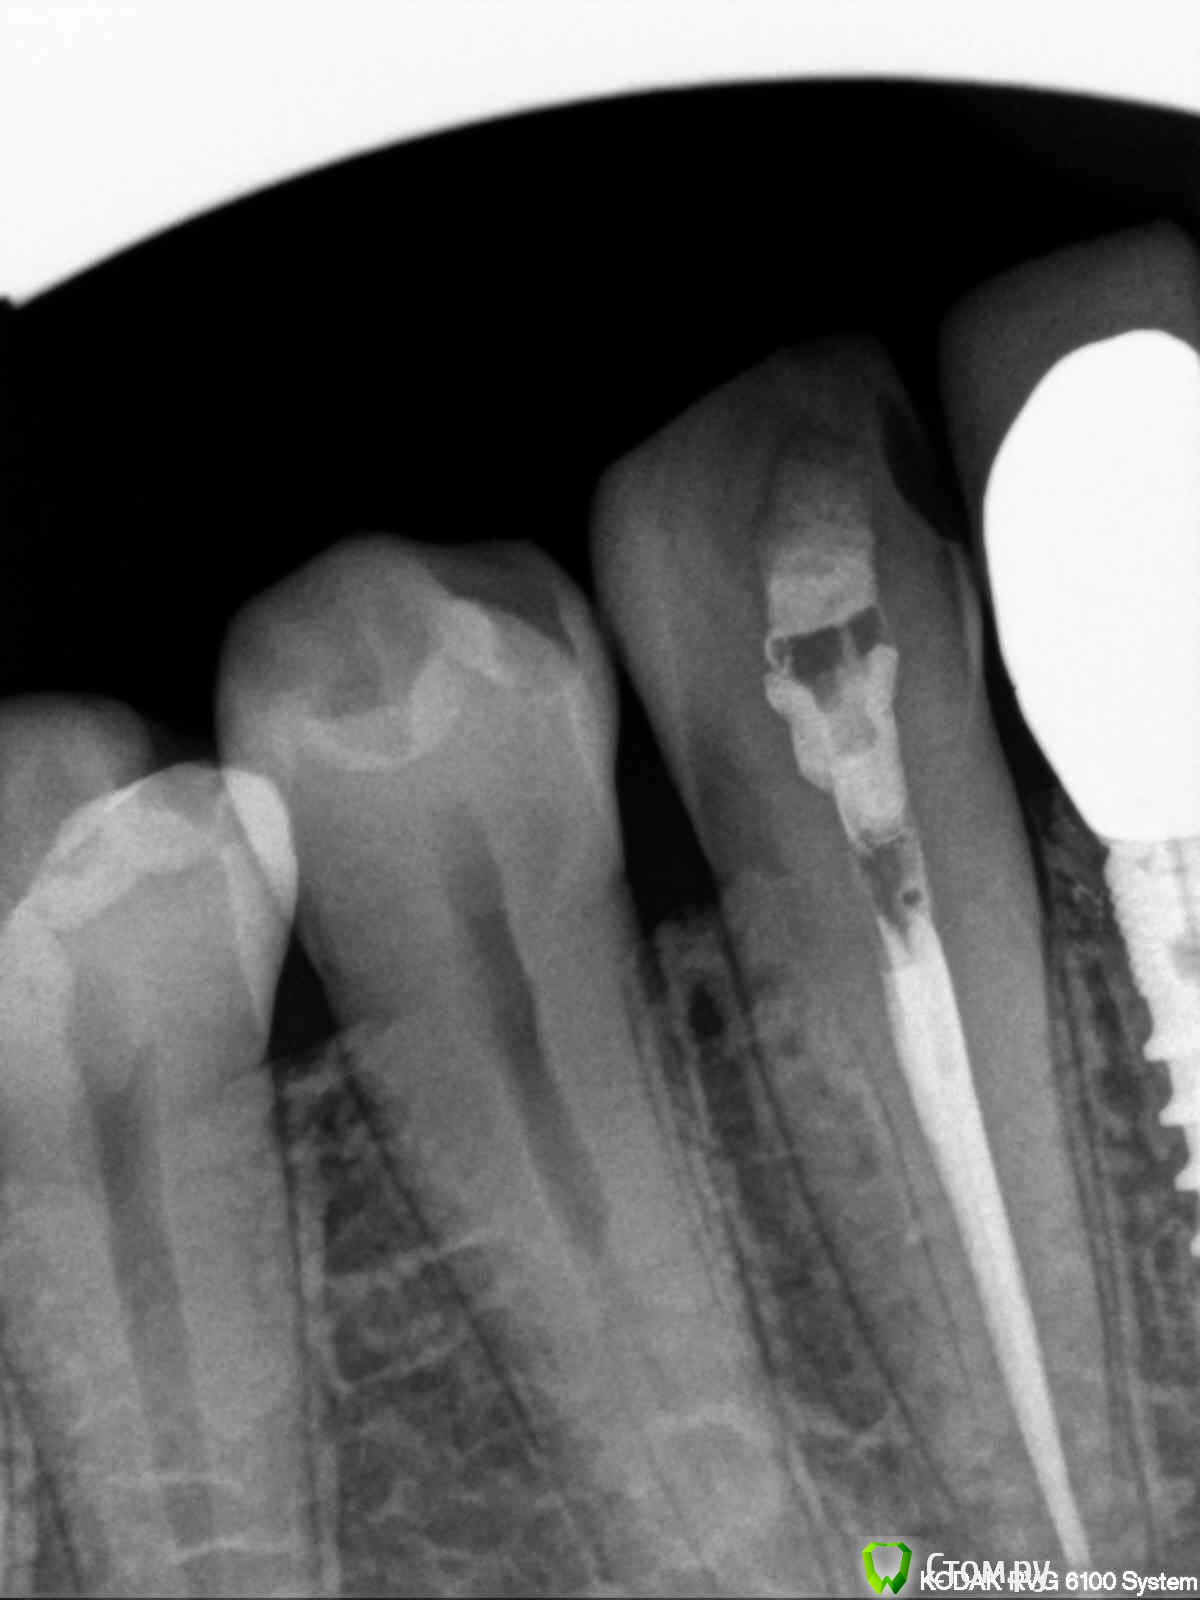

englishlady Опубликовано 16 декабря, 2013 Поделиться Опубликовано 16 декабря, 2013 Уважаемые врачи, здравствуйте. Позвольте Вас еще раз побеспокоить. В зубе 43 полгода назад лечились каналы. Все это время на зубе временная пломба из цемента. На нем даже возможно образовался кариес. Иногда зуб незначительно ноет. Пред дальнейшим лечением (пломба или коронка) есть необходимость в том, чтобы перелечить каналы? Или лучше не трогать. Снимок прилагаю. Заранее спасибо Ссылка на комментарий

IvanK Опубликовано 16 декабря, 2013 Поделиться Опубликовано 16 декабря, 2013 Здравствуйте,выглядит все хорошо,но если ноет - нужно. Вам бы на очный прием, может и не он ноет.. Ссылка на комментарий